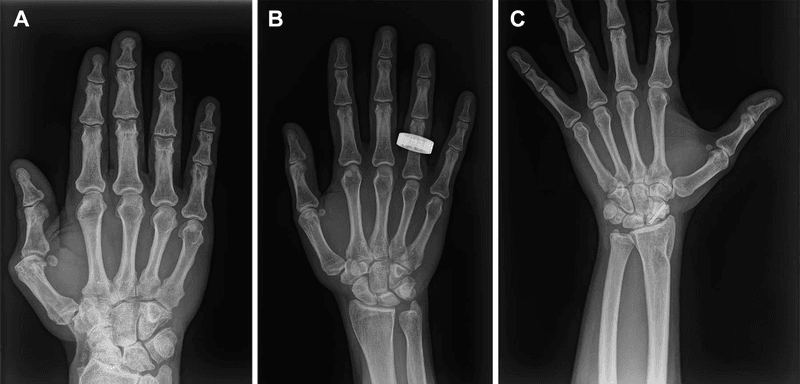

According to the authors of a new study, recreating the beam’s path through Bugorski’s skull was particularly challenging due to a lack of original images or medical documents. All they had to go on was a single, grainy photograph showing the approximate course of the ray through the physicist’s swollen head.

When creating a 3D rendering of the image, however, the authors noticed that the original photo is somewhat deceptive, as it appears to be a profile shot when in fact it depicts a slight rotation of Bugorski’s face. This enabled them to reconstruct the line of damage, which passes mostly through Bugorski’s temporal lobe, close to the point at which it meets the occipital lobe.

The reconstructed proton beam trajectory also crosses the bony labyrinth of Bugorski’s left ear, which makes sense given that he became deaf on this side after the incident. He also experienced numbness on the left side of his face, which the researchers say may be due to the beam damaging either the infraorbital nerve or the temporal bone, before exiting near his left nostril.